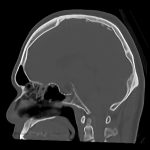

下垂体腺腫

断層撮影

手術前1

No.’15_11 手術前1